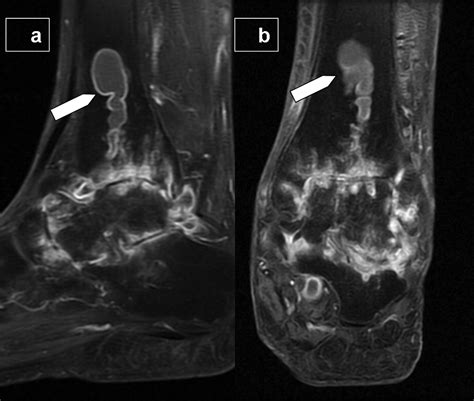

• MRI: In rare cases, an MRI may be used if the cyst is deep-seated or if the doctor needs to visualize its relationship with nearby nerves and blood vessels.